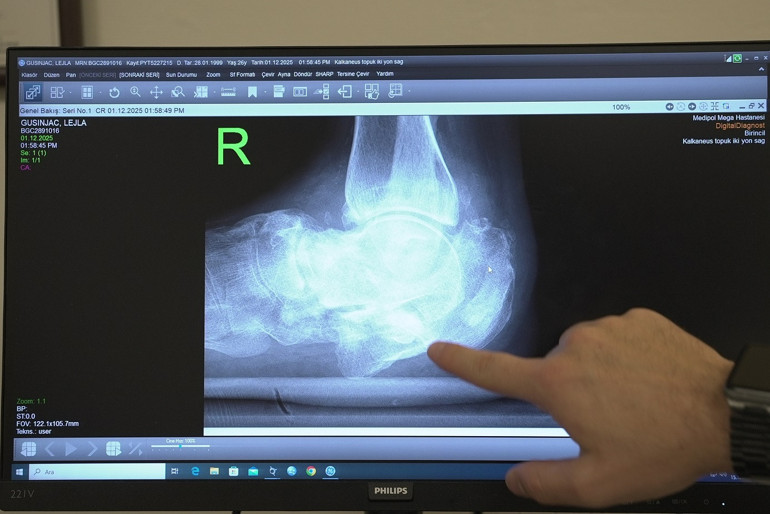

Sırbistan'da diyabete bağlı his kaybı nedeniyle topuğundaki kırığı fark etmeyen ve diz altından bacağın kesilecek denilen Lejla Gusinjac(26), tedavi için Türkiye’ye geldi. Ortopedi ve Travmatoloji Uzmanı Doç. Dr. Bilgehan Çatal ve ekibi, hastanın kalça kemiğinden aldıkları parçayla topuk kemiğini yeniden yapılandırarak genç kadını ampütasyon (uzuv kesilmesi) riskinden kurtardı. Lejla Gusinjac, “Ayağımı kurtardığınızı öğrendiğim an hayatım yeniden başladı”dedi.

Uzun yıllardır kontrolsüz diyabetle mücadele eden 26 yaşındaki Sırbistan vatandaşı Lejla Gusinjac, iki yıl önce merdivenlerden düştüğünde diyabetin neden olduğu his kaybı yüzünden ayağındaki kırığı fark etmedi. Ayağının üzerine basmaya devam eden genç kadına, kendi ülkesinde “Ayağın çürüdü, kesilmesi gerekiyor” denildi. Gusinjac'ın tedavi olma umuduyla Türkiye'ye geldi. Doç. Dr. Bilgehan Çatal ve ekibinin uyguladığı özel kurtarma cerrahisi sayesinde ampütasyon riskinden kurtuldu.

Diyabetle gelen sağlık sorunlarına değinen Doç. Dr. Çatal, “Hastamız 26 yaşında ve uzun yıllardır kontrolsüz diyabeti bulunuyor. Diyabet hastalarında ayaklarda his kaybı oluşabiliyor. Bu nedenle küçük bir kırık bile fark edilmeden ilerleyerek ciddi deformasyonlara yol açabiliyor. Hastamızda topuk kemiğinde, yani kalkaneus dediğimiz kemikte ciddi bir kırık gelişmiş. Üzerine basmaya devam ettikçe ayağında genişleme oluşmuş. Ameliyatta topuk kemiğini yeniden yapılandırdık. Kalça kemiğinden aldığımız kemik greftleriylebir ‘kurtarma cerrahisi’ uyguladık. Amacımız, hastanın ağrısız ve düzgün basabileceği, normale en yakın anatomiyi sağlamaktı. Bu hedefe ulaştık.” diye konuştu.